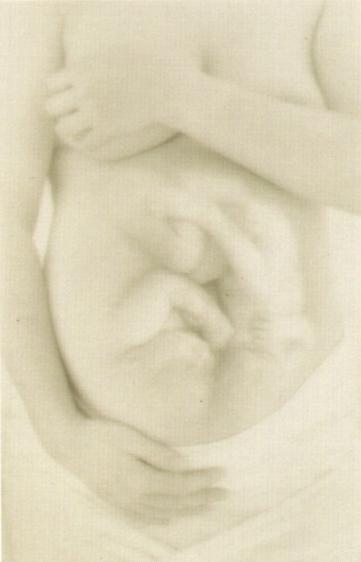

Esta es una guia sobre el

embarazo. Por supuesto no

pretendo que la sigas al

pie de la letra ni decirte

lo que tienes que hacer, yo

soy aferrima defensora de

"Es mi cuerpo, hago lo que

me da la gana", pero creo

que resulta interesante

tener algunas nociones

sobre los cuidados que

deberias seguir. Espero

que te sirva de ayuda.